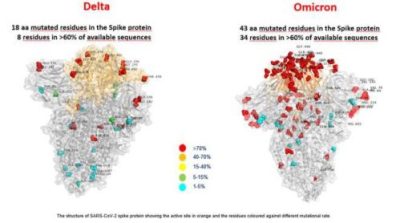

I ricercatori avvertono che i risultati dello studio non sono direttamente applicabili ad omicron perché il comportamento di questa specifica variante dipenderà dall’interazione tra il proprio insieme unico di mutazioni – almeno 30 nella proteina spike virale – e da come compete con altri ceppi attivi circolanti nelle popolazioni di tutto il mondo. Tuttavia, hanno affermato i ricercatori, lo studio fornisce importanti indizi su particolari aree di interesse per omicron e funge anche da primer su altre mutazioni che potrebbero apparire in varianti future.

Questo livello di evoluzione complessa non era stato visto in ceppi diffusi del virus al momento in cui i ricercatori hanno iniziato i loro esperimenti.Ma con l’emergere della variante omicron, questo livello di mutazione complessa nel dominio di legame al recettore non è più ipotetico.La variante delta aveva solo due mutazioni nel suo dominio di legame al recettore e gli pseudotipi studiati dal team di Abraham avevano fino a sette mutazioni, omicron sembra averne quindici, incluse molte delle mutazioni specifiche che il team ha analizzato.

In una serie di esperimenti, i ricercatori hanno eseguito test biochimici per vedere come gli anticorpi si sarebbero legati alle proteine spike contenenti mutazioni di fuga. Molte delle mutazioni, comprese alcune di quelle trovate in omicron, hanno permesso agli pseudotipi di eludere completamente gli anticorpi terapeutici, compresi quelli trovati nelle terapie con cocktail di anticorpi monoclonali.